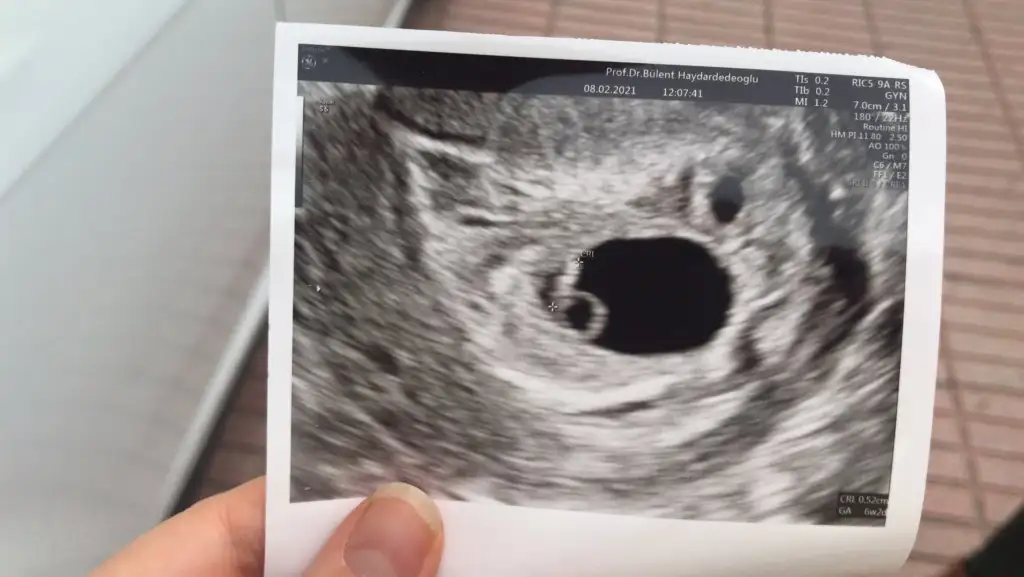

Kiz sankiEki Görüntüle 2777702 Eki Görüntüle 2777703 Eki Görüntüle 2777704 6+4 7+4 11+4 yorumlayabilir misiniz? Henüz belli olmadı cinsiyetimiz

Bu arada üstten ultrasondur. 8 haftalık ben plasentayi sağda gördüm. Yanlış görmedim isem tabi ama yorumlayamadim... Yorumlarınızı bekliyorum...Benim bebeğim de 8 haftalık burada plasenta sağda gibi geldi. Ama yorumlayamadim.. yorumlarınızı bekliyorum ramzi teorisi ile

bence kız sağ tarfta plasentaEki Görüntüle 2780164 Eki Görüntüle 2780165 merhabalar bir tahmin de ben isteyeyim 9+3 ve 7+² ye ait fotoğraflar her ikisi de karından usg

Plasenta solda gibiBenim bebeğim de 8 haftalık burada plasenta sağda gibi geldi. Ama yorumlayamadim.. yorumlarınızı bekliyorum ramzi teorisi ile

Erkek sankiEki Görüntüle 2780164 Eki Görüntüle 2780165 merhabalar bir tahmin de ben isteyeyim 9+3 ve 7+² ye ait fotoğraflar her ikisi de karından usg